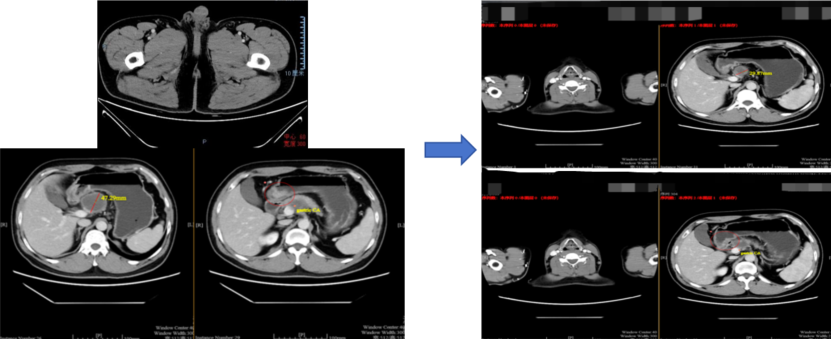

治疗2周期后(2021年10月8日):复查CT示靶病灶淋巴结缩小至35mm,缩小26%,疗效评估为疾病稳定(SD)。

c9b2e20a-a23e-4d1f-b6ce-211177146e98.png

治疗前对比治疗2周期后疗效评估

治疗3周期后(2021年11月3日):复查CT示靶病灶淋巴结缩小至29.9mm,缩小37%,疗效评估为部分缓解(PR)。

e51f106d-3b8c-421b-a587-6b609a7a1db6.png

治疗前对比治疗3周期后疗效评估